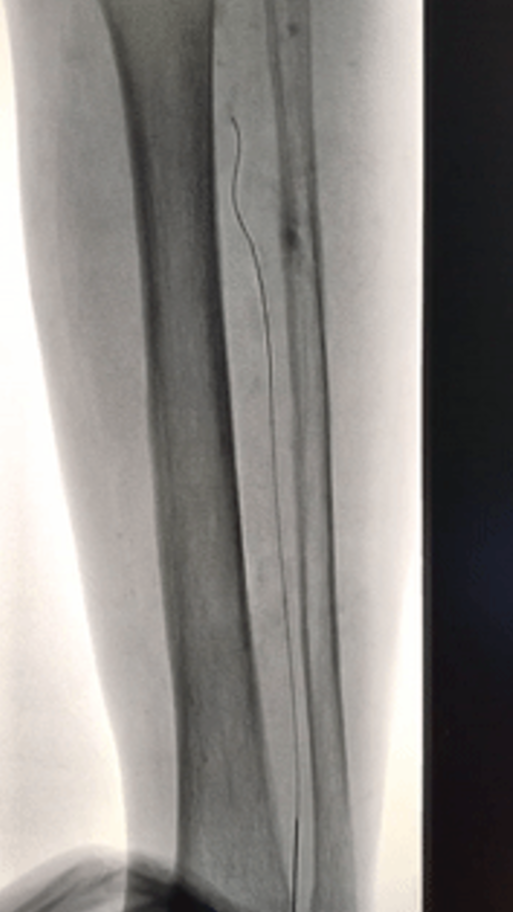

Case 4:另一例膝下三支闭塞,仅腓动脉远端通过侧支供应足底。正向开通腓动脉后,胫后及胫前仍无法进入真腔,遂穿刺足底动脉,将导丝逆行送至踝部,与正向导丝会师后完成扩张,最终开通足底动脉。

当逆向导丝无法进入正向真腔时,可采用导丝对吻技术:将逆向导丝留置作为标记,引导正向导丝前进。若两者均在假腔内,则可应用球囊扩张假腔(CART或Reverse-CART),为导丝进入真腔创造条件。

Case 5:正向导丝经胫前进入,逆向导丝经足底上行,在踝部无法汇合。先后扩张正向球囊和逆向球囊后,导丝顺利进入同一腔道,成功开通足弓。

Case 6:采用双球囊对吻技术:正向使用外周球囊,逆向使用冠脉球囊,在6F鞘内同时扩张2mm重叠段,导丝顺利通过。